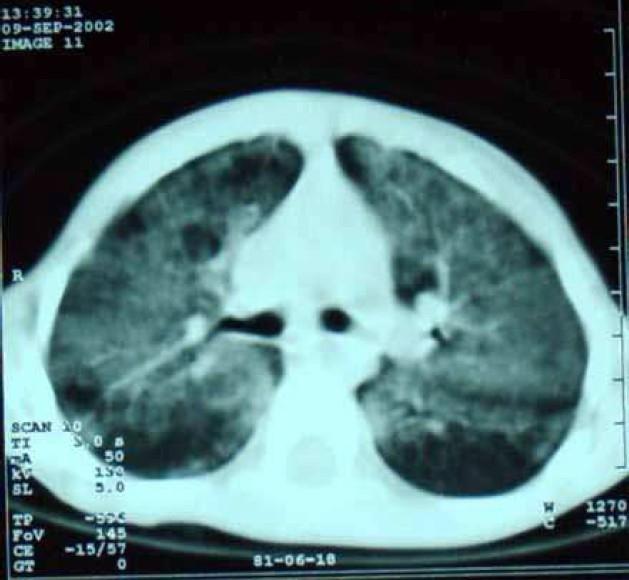

Pulmonary alveolar proteinosis, (PAP) is a rare disease of unknown etiology, characterized by accumulation of intraalveolar proteinaceous material which is rich in lipid and positive on periodic acid-Schiff stain. Two clinically different pediatric types have been defined as congenital PAP which is fulminant and fatal, and a late-onset PAP which is similar to the adult form and less severe. Eight children with late-onset PAP were hospitalized from 1998 to 2005 in Mofid Children Hospital. Characteristics of these patients and the methods of diagnosis and treatment are presented in this case series.

肺泡蛋白沉积症(PAP)是一种病因不明的罕见疾病,其特征是肺泡内富含脂质的蛋白质物质积聚,且过碘酸-希夫染色呈阳性。临床上已定义了两种不同的儿科类型,即暴发性且致命的先天性PAP,以及与成人形式相似且病情较轻的迟发性PAP。1998年至2005年期间,8名迟发性PAP患儿在莫菲德儿童医院住院。本病例系列介绍了这些患者的特征以及诊断和治疗方法。